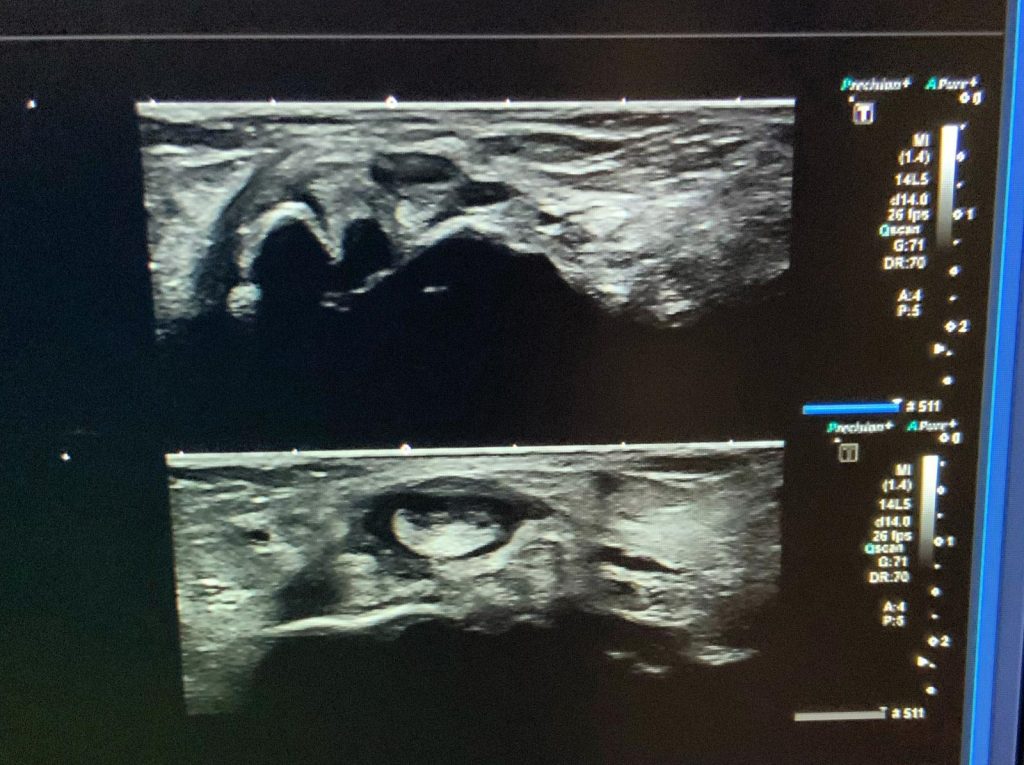

En nuestra clínica, realizamos ecografías de pies como parte de un enfoque integral para el diagnóstico y tratamiento de diversas patologías. La ecografía es una técnica de imagen no invasiva que nos permite visualizar en tiempo real los tejidos blandos, tendones, ligamentos y otras estructuras del pie, lo que facilita un diagnóstico preciso y detallado.